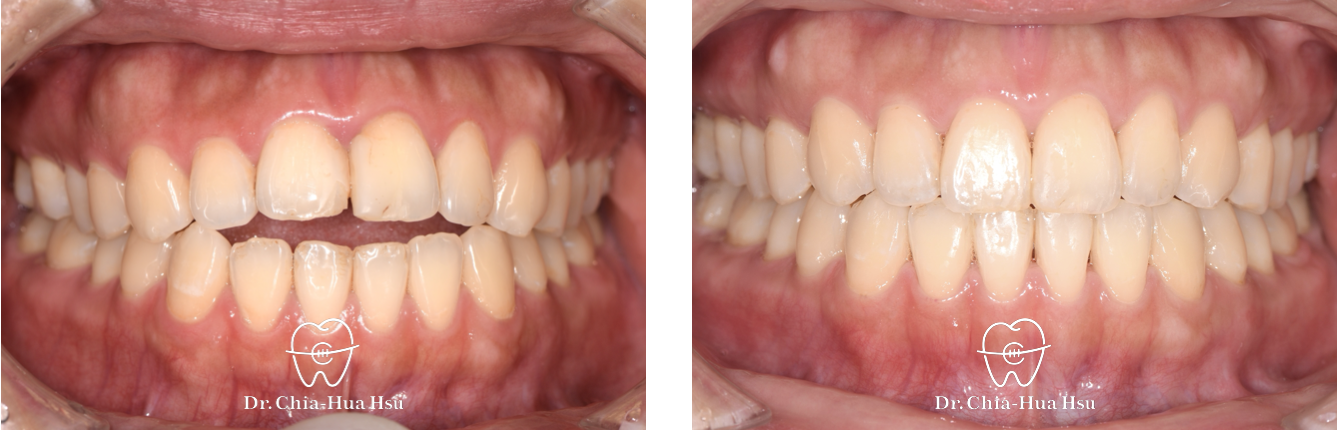

治療前

治療後

• 治療結果:咬合恢復正常,微笑曲線更自然!